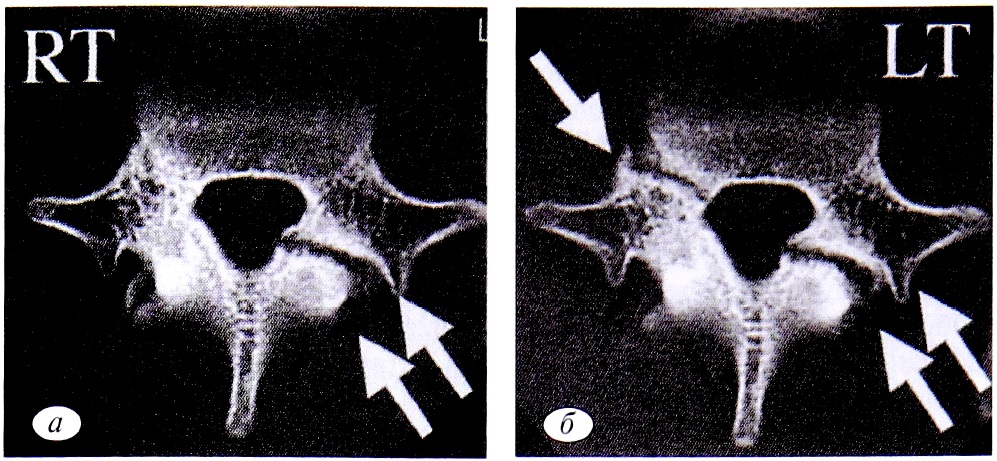

О значительных трофических нарушениях в области спондилолиза свидетельствуют наблюдения, при которых отсутствовали признаки регенерации в пораженной дуге позвонка в течение длительного времени [1, 12, 29]. В противоположной же дуге и ножке отмечались реактивный склероз и даже их гипертрофия. Необычная реакция отражает физиологический ответ на нестабильность [31]. Это предположение было подтверждено при биомеханическом исследовании К. Sairyo и соавт. [25]: пациентов с односторонним спондилолизом, продолжающих активные занятия спортом, в результате аккумуляции нагрузки (особенно ротации в сочетании с осевой нагрузкой) в области неповрежденной дуги развивается реактивный склероз или же возникает стрессовый перелом этой дуги. При рентгенологическом исследовании в ранней стадии спондилолиза реактивный склероз контралатеральной дуги еще не определяется. Он становится видимым в прогрессирующей стадии заболевания. Эти клинико-рентгенологические наблюдения свидетельствуют об усилении нагрузки на контралатеральную дугу, приводящей к склерозу или стрессовому перелому (рис. 7).

Рис. 7. Данные аксиальной КТ позвонка Lv [25]. а — первоначальное обследование — левосторонний спондилолиз (две стрелки); б — через 2 мес — стрессовый перелом правой ножки дуги (одна стрелка). КТ — компьютерная томография.

Fig. 7. Data of axial CT of the vertebra LV [25]. a — initial examination-left-sided spondylolysis (two arrows); b — after 2 months — stress fracture of the right leg of the arc (one arrow). CT— computer tomography.